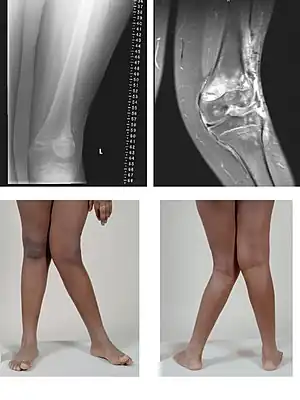

A very severe case of genu valgum of the left knee following bone cancer treatment

a) Genu valgum deformity b) zoomed-in view